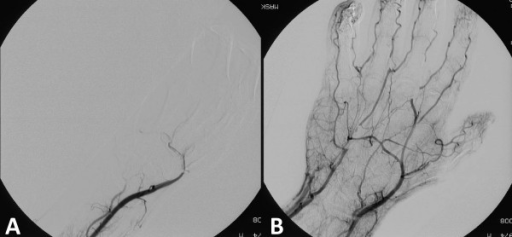

- Phlebothrombosis: Thrombus forms spontaneously without prior inflammation; clot attached loosely

Phlebothrombosis of the right leg in a child with venous malformation. The right leg is somewhat swollen (clearly visible at the ankle) and slightly bluish-livid discolored. - `